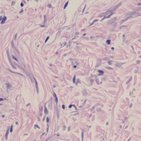

As you’ll know if you’ve ever tried identifying a tissue under a microscope, it’s not easy work. And if you’ve never tried it, simply looking at a collection of different tissue types is enough to send you into panic. That’s why practicing with our connective tissue quizzes is essential!

To start, see if you can connect what you’ve learned in the above videos with the tissue slides you see on the connective tissue worksheet below. A labeled version of the tissue identification worksheet is available for you to make notes - but try to fill in the blanks on the unlabeled diagram first!